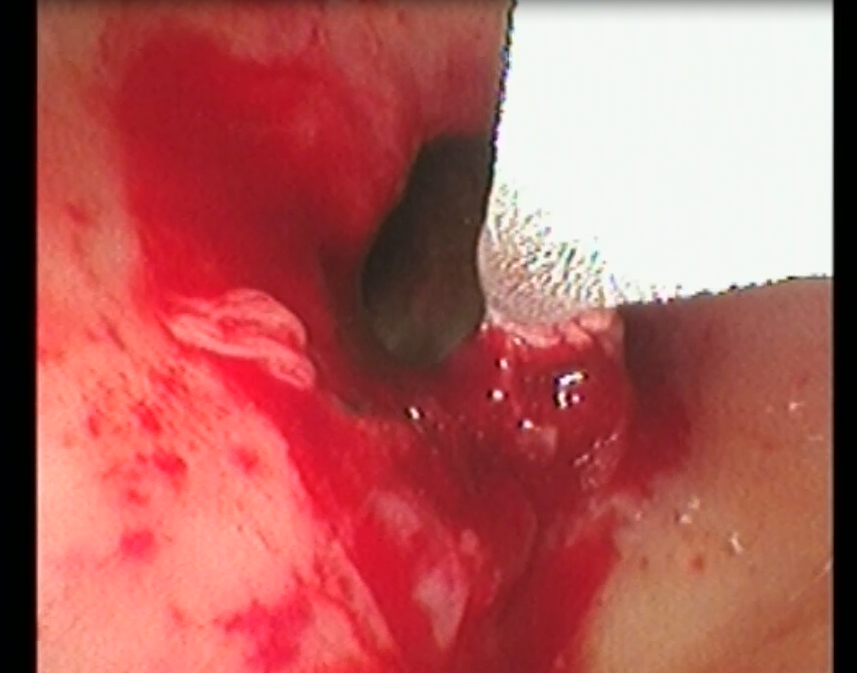

手术中,胸外科团队采用多技术联合操作策略:首先通过常规电子支气管镜完成病变探查与定位,随后置入硬支气管镜建立稳定操作通道,保障术中通气安全。针对气道内增生组织,团队交替使用氩气刀进行精准切除,并应用冷冻治疗仪对残余病灶进行消融与止血。最后在硬镜支撑与细支气管镜引导下,完整取出原有气管支架,未对气道黏膜造成附加损伤。

▲术中冷冻治疗

▲气道肿物清除术后图